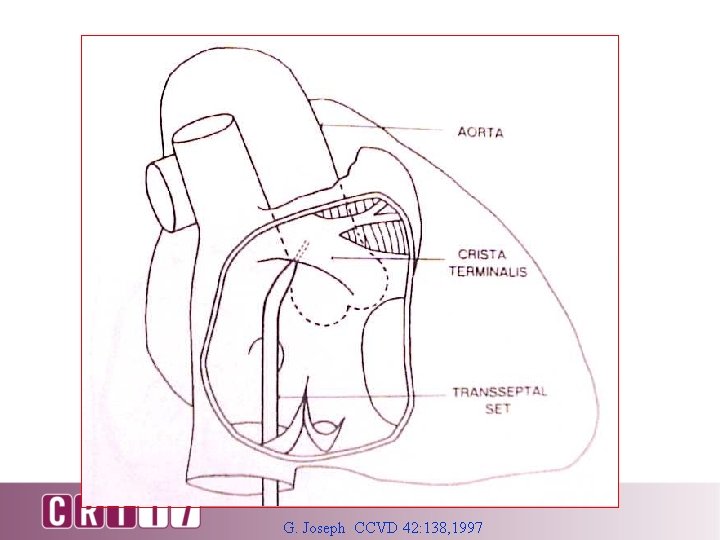

G. Joseph CCVD 42: 138, 1997